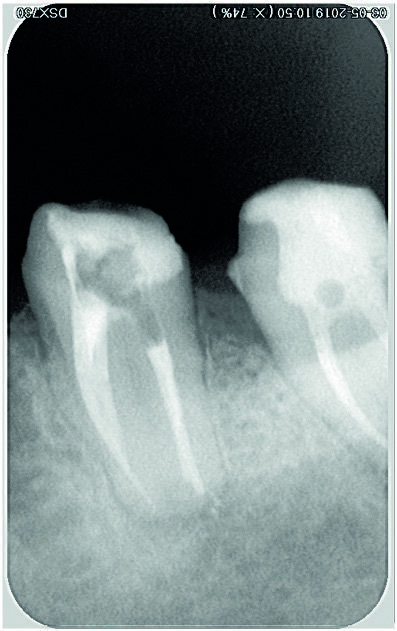

Figs. 15 et 16 : Radiographie après obturation.

Fig. 17 : Radiographie prise lors du suivi à neuf mois.

Le système de lasso choisi est le dispositif EndoCowboy en raison des caractéristiques et de la résistance du fil (fil de 0,1 mm en acier inoxydable étiré ayant une excellente résistance à la rupture, et tube de 0,4 mm ; Köhrer Medical Engineering). Conformément aux instructions du fabricant (Figs. 8 et 9), le dispositif est manipulé par deux praticiens travaillant en commun — l’un étant chargé d’observer au microscope la position de la boucle du lasso autour du fragment fracturé, et l’autre de manipuler le dispositif (serrage du lasso autour du fragment. Après avoir solidarisé le fragment et la boucle, l’ensemble est alors retiré par de légers mouvements de va-et-vient verticaux (Figs. 10–13). Tous les canaux sont instrumentés avec des limes D-Finder de taille 8, 10, 12 et 15 (MANI) pour obtenir manuellement une trajectoire de glissement (glide path). Le nettoyage et la mise en forme de tous les canaux radiculaires sont réalisés à l’aide de limes Silk (MANI) de taille croissante (jusqu’à 25/0.06) et du moteur endodontique Tri Auto ZX2 (Morita). Un protocole d’irrigation à l’hypochlorite de sodium à 5,25 % est assuré tout au long du traitement. L’irrigation finale est accomplie avec une solution d’EDTA à 17 % et d’hypochlorite de sodium à 5,25 %, activée par une technique manuelle d’activation dynamique. La technique de condensation hydraulique est utilisée pour réaliser l’obturation avec des cônes de gutta-percha à 4 % et le ciment de scellement BioRoot RCS (Septodont) (Figs. 14–16). La cavité pulpaire est scellée au moyen d’un ciment verre ionomère modifié par adjonction de résine, Ionoseal (VOCO), et une restauration provisoire est préparée.

La patiente avait été adressée à notre cabinet dentaire pour une restauration coronaire définitive. Lors de la visite de suivi six mois après, la dent s’est révélée asymptomatique (Fig. 17).